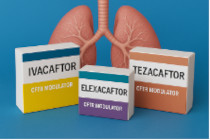

Aggiornamento

Fibrosi cistica 2025: stato dellarte e novità

Maschio M, Grazian F, Traunero A, Ghirardo S, Amaddeo A.

Una delle patologie croniche genetiche con i più grandi progressi negli ultimi anni. Un Aggiornamento completo, dallo screening neonatale all'uso dei farmaci modulatori della proteina CFTR: un cambio di paradiga.